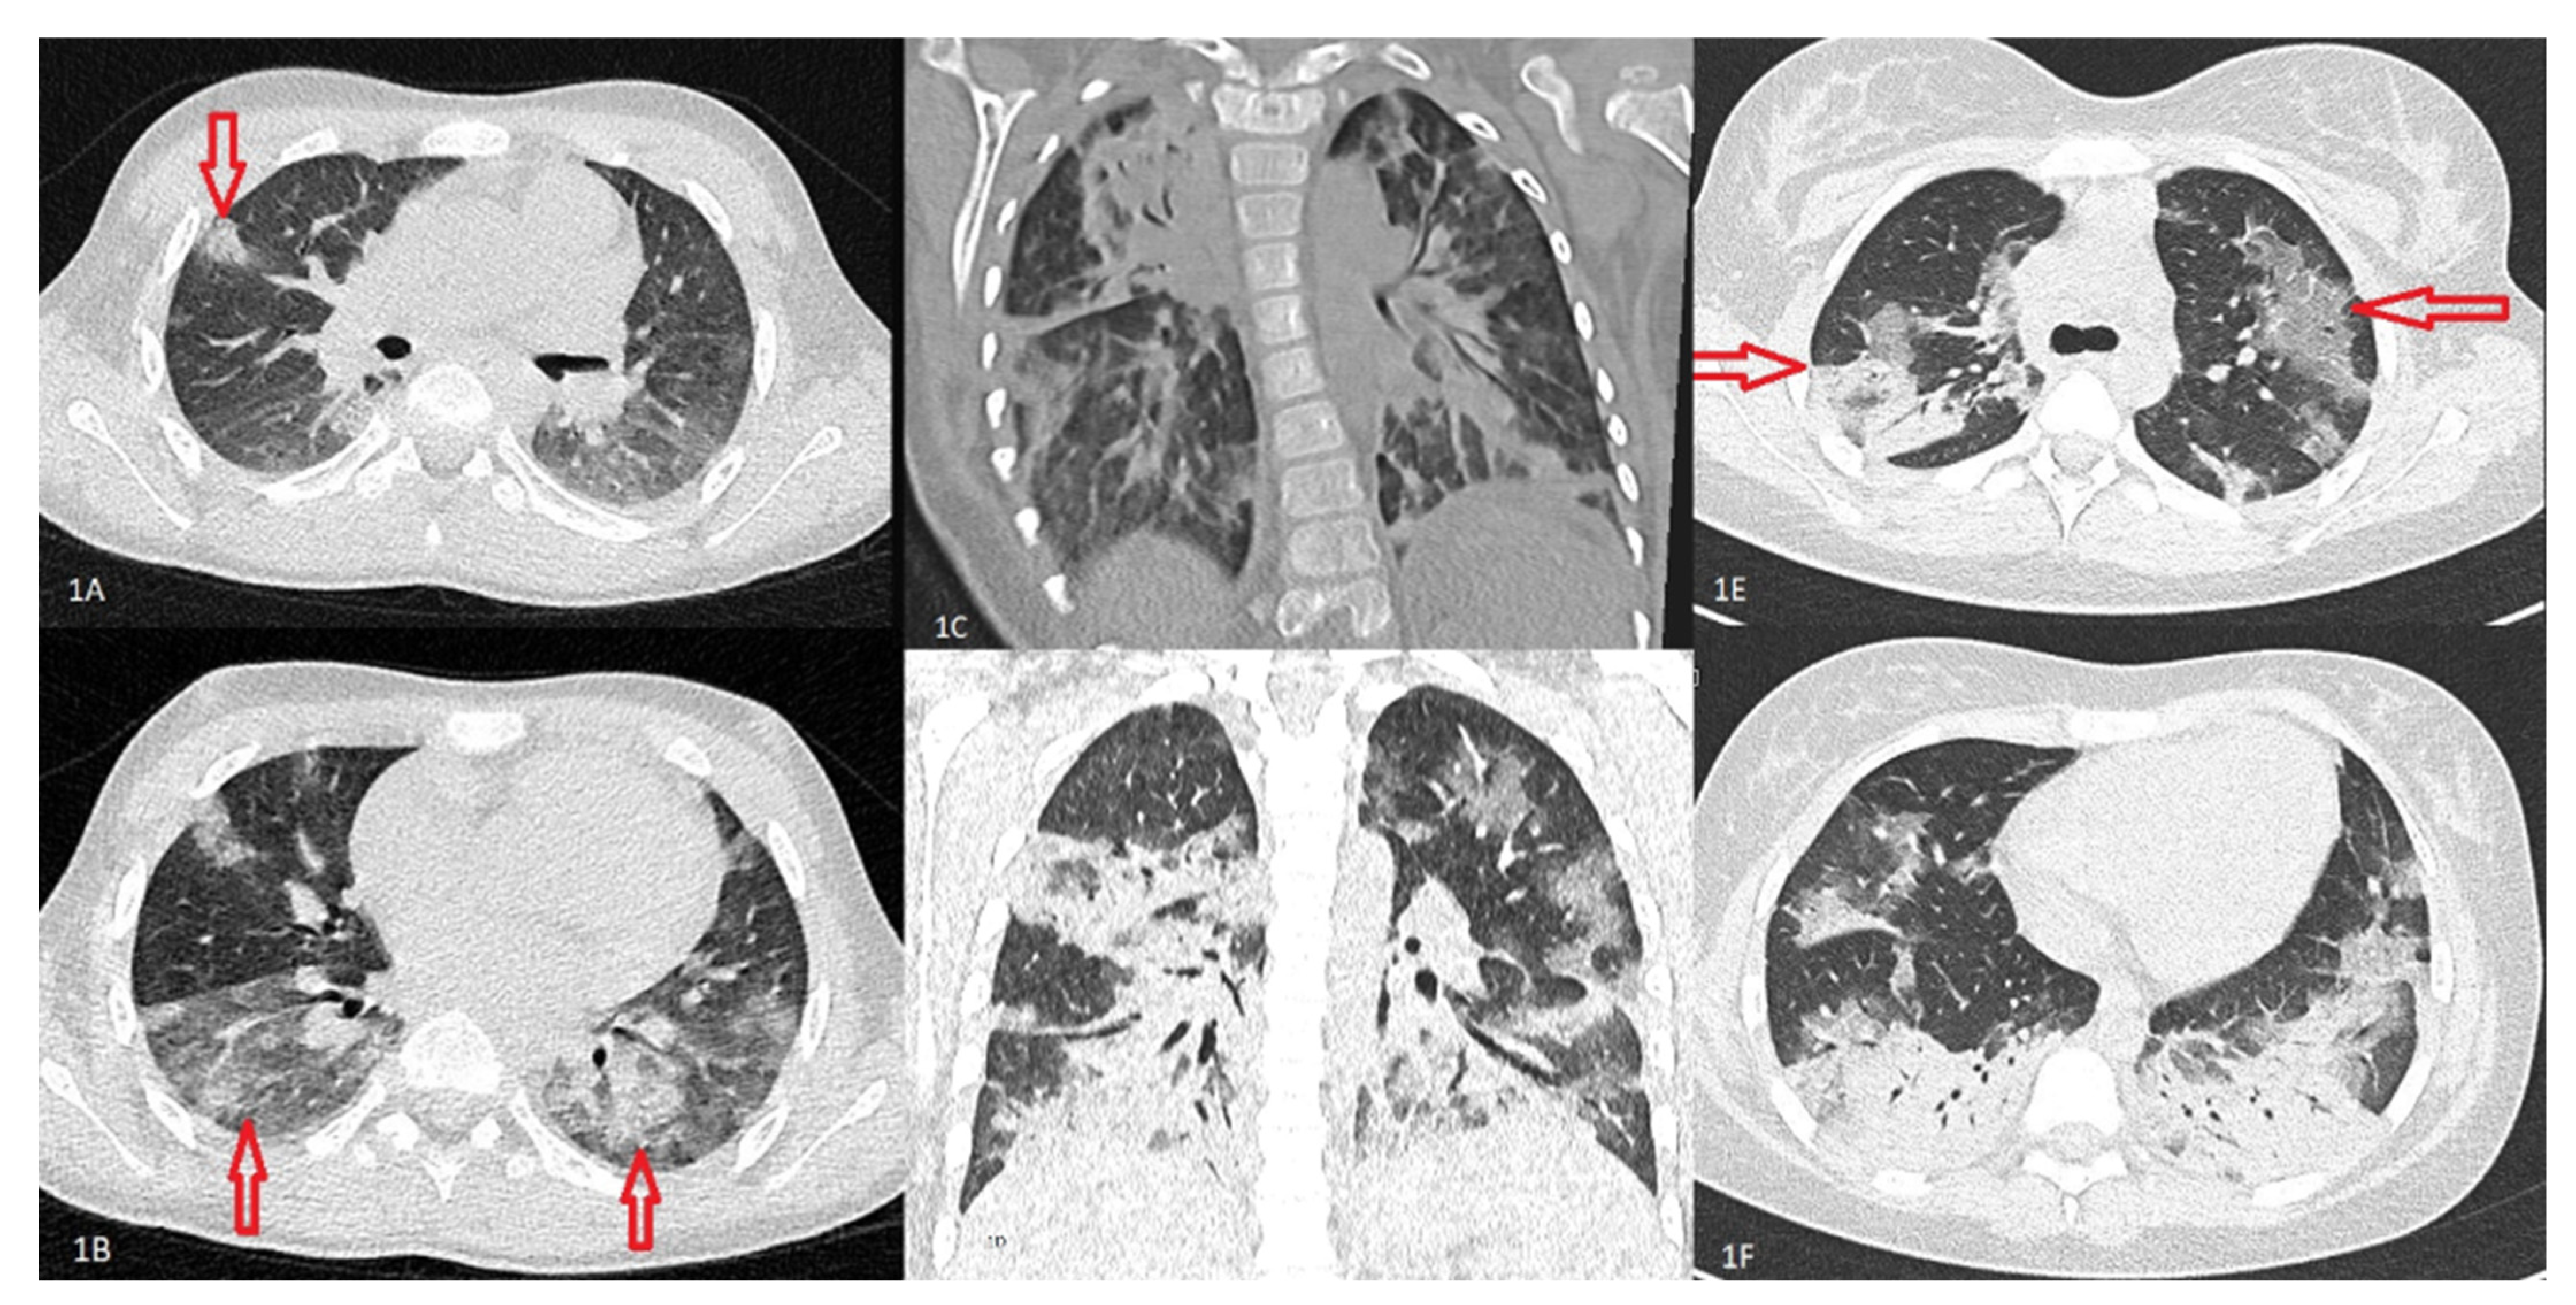

2.5. Imaging

- Palabiyik, F.; Kokurcan, S.O.; Hatipoglu, N.; Cebeci, S.O.; Inci, E. Imaging of COVID-19 pneumonia in children. Br. J. Radiol. 2020, 93. [Google Scholar] [CrossRef]

| PBT II GGO II + GGO | 52 (19.48%) - 1 (0.38%) - | 3 (9.68%) 26 (83.87%) - - | 2 (6.89%) 21 (72.41%) - 3 (10.34%) | - 4 (80.00%) - 1 (20.00%) | <0.0001* |